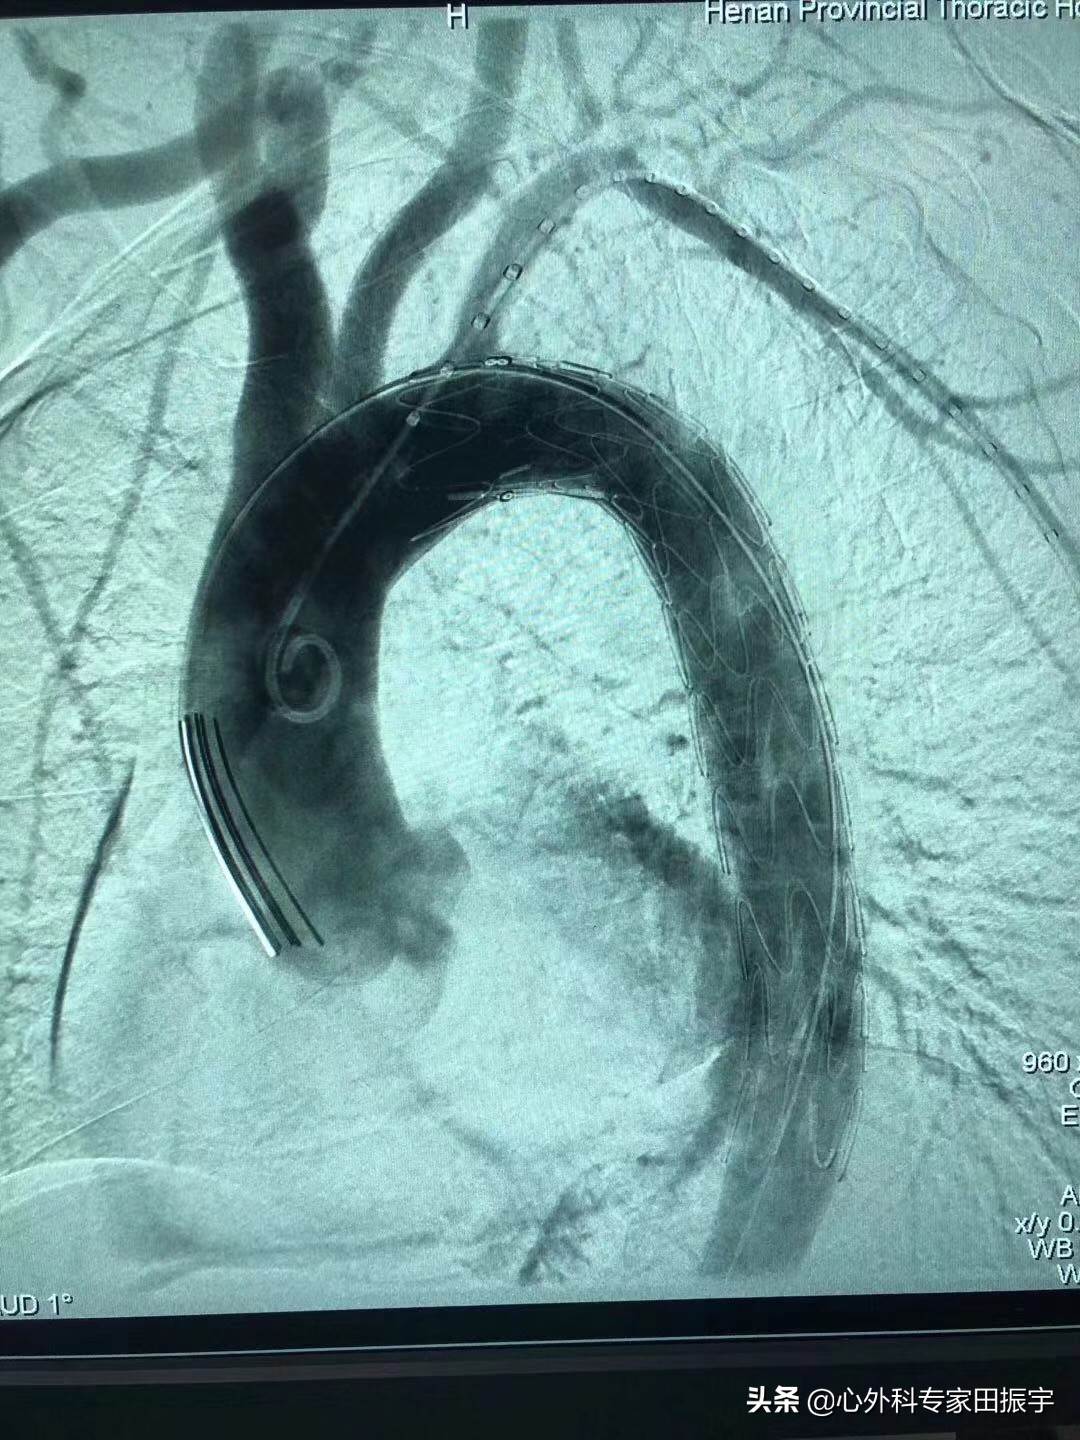

ACC/AHA 指南建议,结缔组织病合并慢性主动脉夹层患者,胸降主动脉直径超过5.5厘米时,进行开放式手术修复(I类推荐,证据B)。通常,象鼻子手术也是必需的。在主动脉弓和胸降主动脉近端手术中,使用右腋动脉/锁骨下动脉插管和低温停循环实现大脑和全身保护。2012年,EACTS/ESC/EAPCI 建议仅针对复杂的 B 型夹层进行 TEVAR治疗。EACTS/ESC/EAPCI将复杂B型夹层分为急性期和慢性期:急性或亚急性/慢性。急性期并发症包括持续疼痛、难治性高血压、内脏器官灌注不良和破裂、低血压或休克迹象。慢性期并发症包括主动脉直径大于5.5厘米,直径增加4毫米/年,难治性高血压,复发性内脏器官灌注不良,或复发性症状。然而,FDA和美国胸外科协会、胸外科学会、血管外科学会和介入放射学学会在内的多学科小组委员会已同意将"复杂”夹层的定义仅限于破裂、即将破裂或远端内脏器官灌注不良。

B型主动脉夹层介入治疗后DSA影像

B型主动脉夹层介入治疗前DSA影像